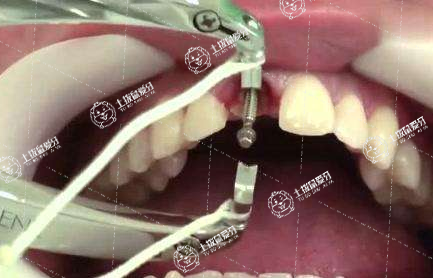

種植牙是效果是牙齒修復(fù)里面最好的,種植牙雖然不是人類天然長出來的牙齒,但是人工牙根在植入牙床后能夠與骨組織完全融合,而成為身體的一部分。至今,種植牙臨床應(yīng)用已超過40年,全世界每年有數(shù)以百萬計的牙種植體為患者解決了缺牙的痛苦

種植系統(tǒng)在生產(chǎn)工藝、外形設(shè)計、連接方式、加工精度、上部結(jié)構(gòu)以及消毒包裝等方面都有嚴格的要求及標準。不同的種植系統(tǒng)及材料就會有不同的效果,而這個也是決定種植出來的牙齒能維持多久的效果的重要因素了。

種植牙手術(shù)屬外科手術(shù),其對修復(fù)技術(shù)的精度要求極高,醫(yī)生必須接受過專門的學習和培訓。同時具有一定的臨床經(jīng)驗,才能正確完成種植治療的每一個步驟,順利處理治療過程中遇到的各種特殊情況,從而保證種植牙的長期效果。